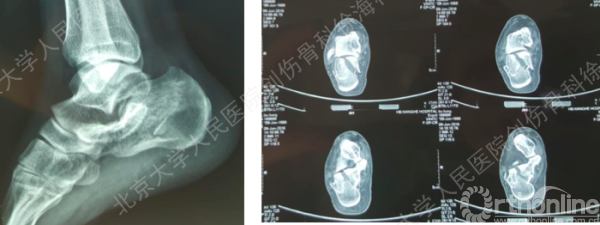

年龄:26岁

性别:男性

病因:高处坠落伤

病情:跟骨骨折(Sanders II型)

CT扫描图